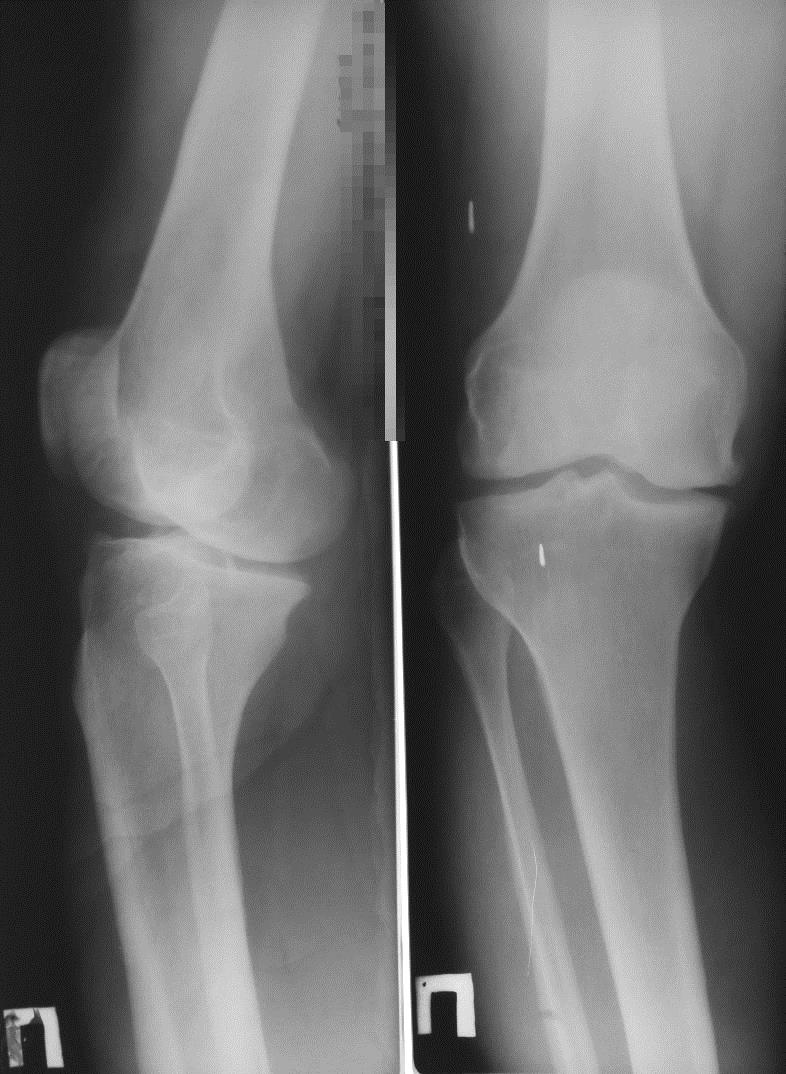

Замена коленного сустава необходима, когда происходит износ и разрушение сустава, что нарушает его функционирование. В 85% случаев показанием к проведению операции служит гонартроз третьей степени. При этой болезни гиалиновый хрящ изнашивается, развивается разрушение костей, образующих коленный сустав, деформация конечности. В результате возникает выраженный болевой синдром.